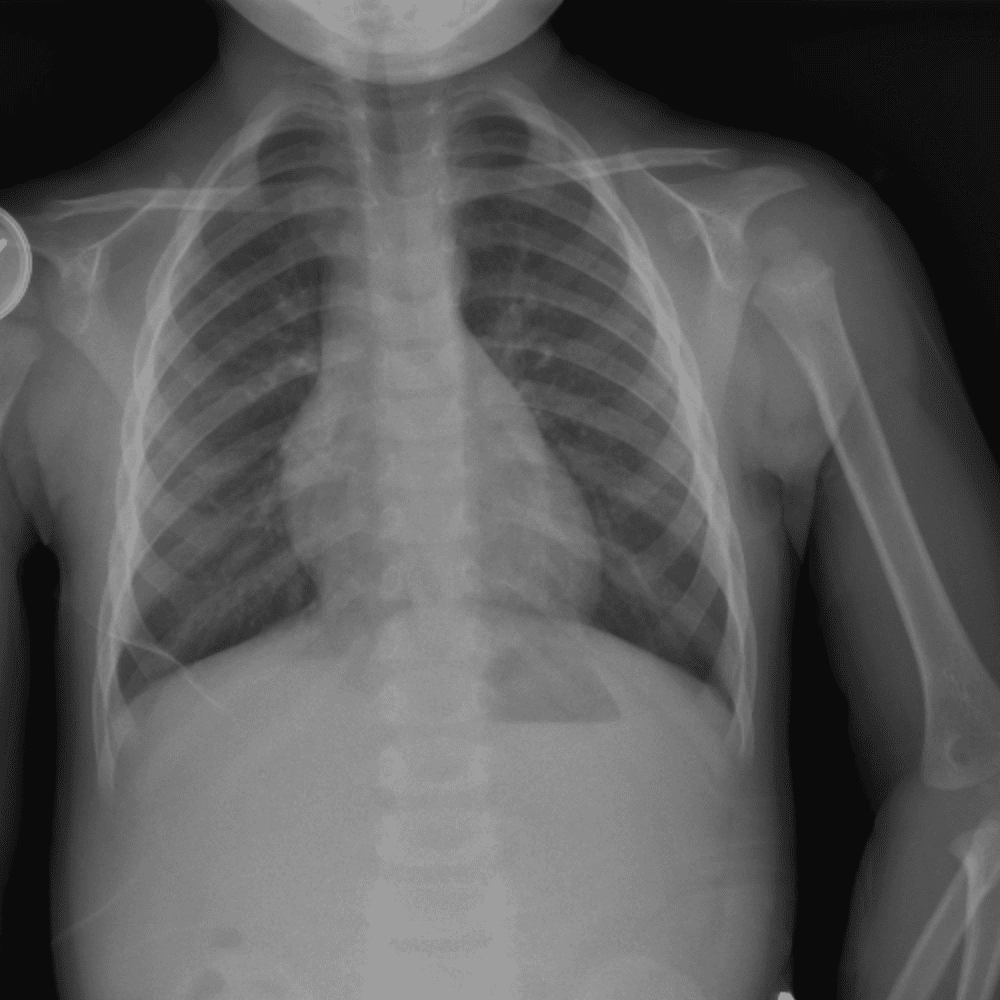

Peds Chest

Practice

Simulates call by including subtle or difficult cases and some normals.

50 cases